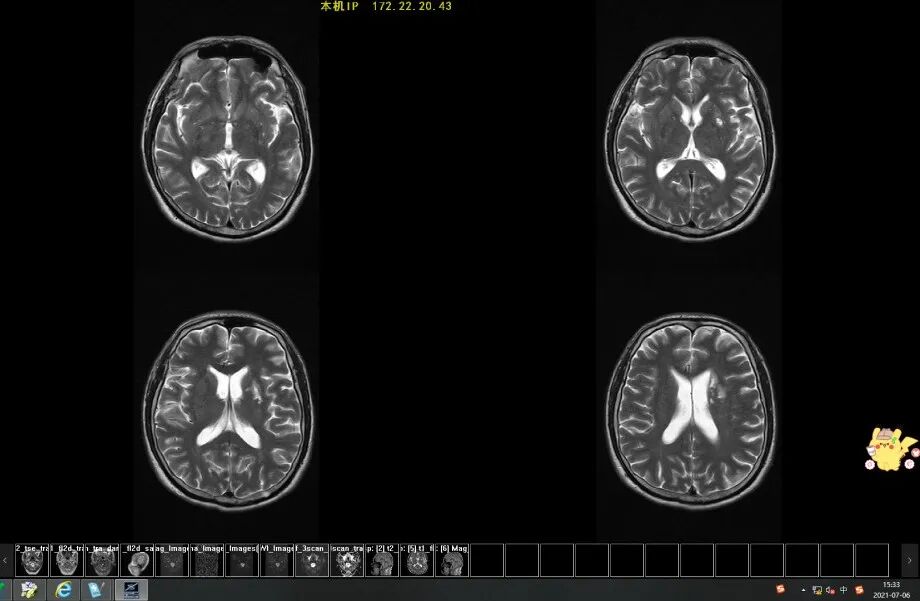

病例二

患者,男,65歲,因頭暈10天伴右側(cè)肢體無力1天入院,入院診斷為腦梗死,經(jīng)過積極治療,現(xiàn)已康復(fù)出院。

患者CT檢查影像